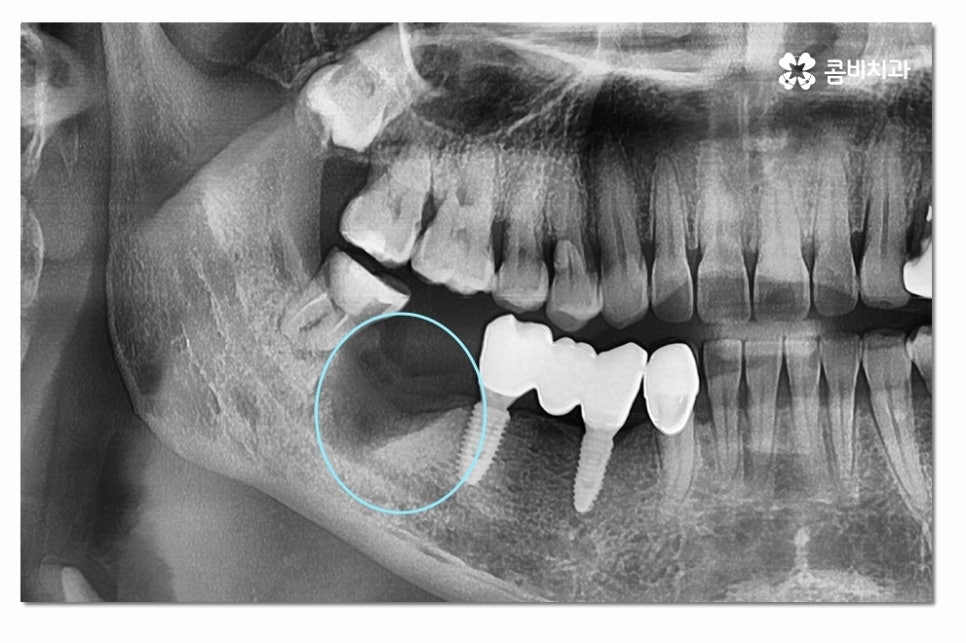

위 사진처럼 어금니를 발치한 후에는 잇몸이 차오르길

기다리게 되고 임플란트를 식립할 잇몸 뼈가

충분한지 잇몸 상태를 정밀 검진을 통해 확인하는 과정을

거치며 잇몸이 부족한 경우에는 뼈이식을 받아야 할 수 있어요.

잇몸이 점점 흡수되기 때문에 추후에는 어금니임플란트

치료를 하더라도 잇몸 뼈가 부족해서 치료가 어려워지거나

뼈이식을 추가로 받아야 하는 경우도 있어요.